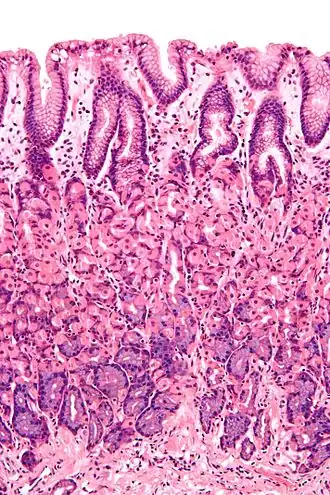

![]() Microscopic section of gastric mucosa. Foveolar cells can be seen at top of the image lining the surface and pits | |

Foveolar cells or surface mucous cells are mucus-producing cells which cover the inside of the stomach, protecting it from the corrosive nature of gastric acid.[1][a] These cells line the gastric mucosa and the gastric pits. Mucous neck cells are found in the necks of the gastric glands. The mucus-secreting cells of the stomach can be distinguished histologically from the intestinal goblet cells, another type of mucus-secreting cell.

Foveolar cells line the surface of the stomach and the gastric pits. They constitute a simple columnar epithelium, as they form a single layer of cells and are taller than their width. Other mucus-secreting cells are the mucous neck cells in the necks of the gastric glands.[2]: 257

Surface mucous cells have large quantities of mucin granules in their apical (top) surface and project short microvilli into the lumen of the stomach.[2]: 257 Mucins are large glycoproteins that give the mucus its gel-like properties.[3] As mucins are lost during routine histology preparation, they stain pale, but if preserved correctly the cells stain strongly with special techniques like PAS or toluidine blue, the last representing the anionic nature of foveolar cell secretions. Below the mucin granules, surface mucous cells have a Golgi apparatus, the nucleus, and small amounts of rough endoplasmic reticulum.[4]: 577 Mucous neck cells are located within gastric glands. These are shorter than their surface counterpart and contain lesser quantities of mucin granules in their apical surface.[4]: 578